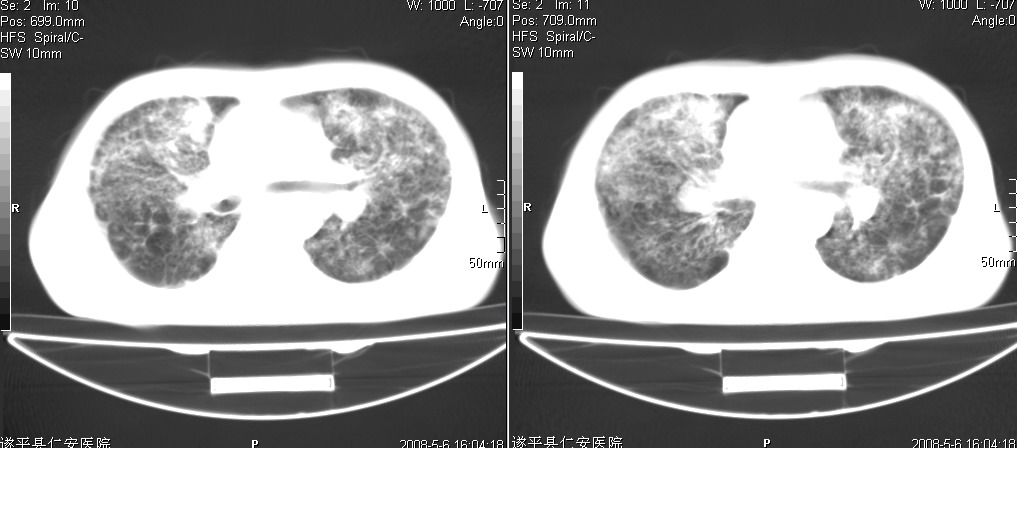

以下是引用光线在2008-5-6 18:36:00的发言:[br]双肺结核(左上肺空洞形成)、间质性改变合并感染,右肺大泡;右侧胸膜增厚。

以下是引用zsl6918在2008-5-7 1:54:00的发言:[br]首先肺泡蛋白质沉着症,其次考虑机遇性感染。